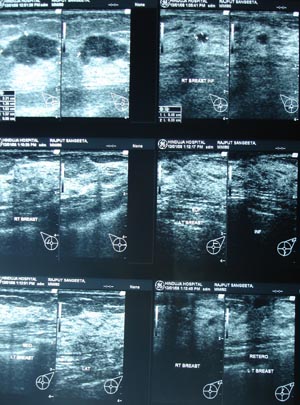

Ultrasonography of breast

The USG is performed with hight frequency (7-10 MHZ) probe. The information is to be correlated with mammography finding.